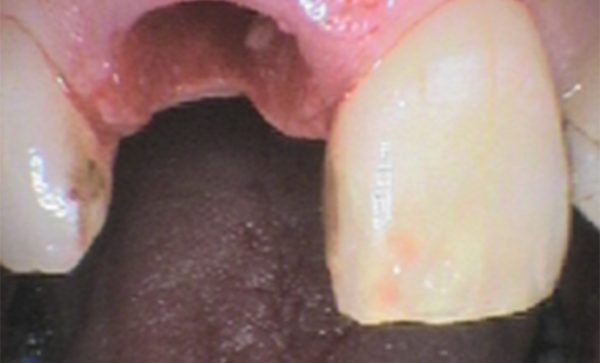

Case 5